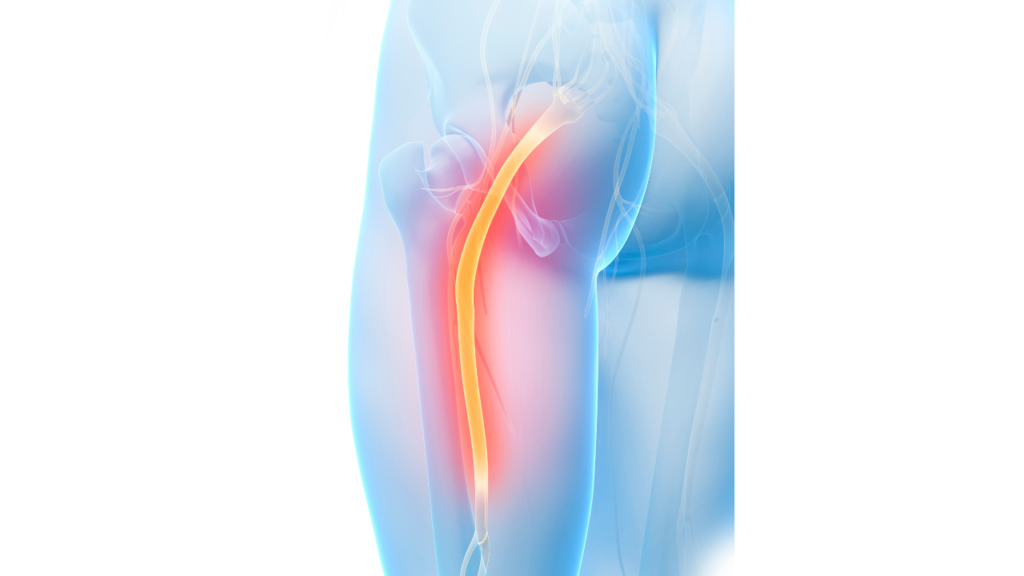

坐骨神経痛は、腰から足にかけて伸びる坐骨神経が圧迫・刺激されることで起こる、非常に辛い症状です。

お尻から足にかけての痛みや痺れ、ふくらはぎの張りや違和感などが特徴で、特に「間欠跛行(かんけつはこう)」と呼ばれる、安静時は楽でも動き出すと痛みが出る状態が多く見られます。